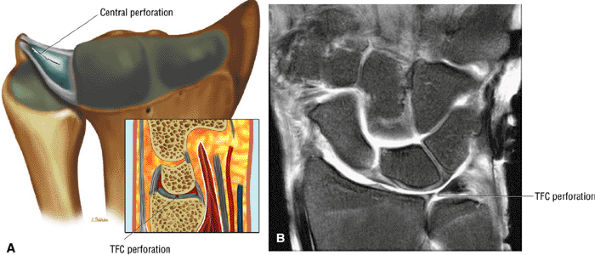

FIGURE 10.70 ● TFC complex. (A) Volar view of the ligaments of the ulnar side of the carpus. The meniscus homologue and meniscus reflection are shown. The meniscus homologue inserts onto the volar surface of the triquetrum. The meniscus homologue shares a common origin from the dorsal ulnar corner of the radius with the TFC. The TFC extends in a volar direction from the meniscus homologue to the base of the ulnar styloid. The ulnolunate component of the ulnocarpal ligament is considered to be part of or a continuation of the short radiolunate ligament. (B) In this dorsal view, the ulnar and dorsal aspect of the TFC complex is invested by a thick ligamentous layer (the meniscus reflection) with proximal attachment to the TFC complex and ulna and distal attachment to the base of the fifth metacarpal. (C, D) The dorsal views of the TFC complex show the dorsal and volar radioulnar ligaments as separate from the articular disc of the TFC. The term TFC refers to the central horizontal articular disc and adjoining volar and dorsal radioulnar ligaments. The term TFC complex refers to the TFC and any additional ulnar ligamentous structures, such as the meniscus homologue, ulnar collateral ligament, subsheath of the extensor carpi ulnaris tendon, and ulnolunate and ulnotriquetral ligaments.